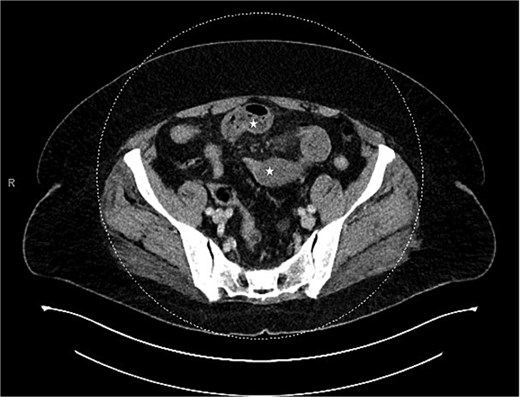

Contrast-enhanced CT of the abdomen and pelvis showed two closely positioned transition points in the right lower quadrant with moderate mesenteric congestion and interloop fluid. Those findings were suggestive of a closed-loop SBO (Fig. 1). The appendix was noted to be unremarkable in caliber but mildly stretched toward the transition point (Fig. 2). An enlarged paraesophageal hernia was also identified.

CT showing closed bowel loop obstruction and two closely positioned transition points.